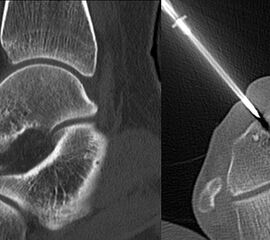

Axiale CT-Aufnahmen eines Osteoidosteoms im Bereich des Calcaneus mit typischer Nidusbildung und perifokaler Sklerose (links). Bildgesteuerte Thermofrequenzablation der Läsion (rechts).

Die klinischen Symptome von Knochentumoren sind bis auf wenige Ausnahmen sehr unspezifisch. Schmerzen, Schwel­lung und Bewegungseinschränkungen können auch von zahllosen anderen krankhaften Prozessen ausgehen, insofern sind dementsprechende anamnestische Angaben nur zum Teil weiterführend. Knochenschmerzen zählen zu den somatischen Schmerzen und werden im Gegensatz zu neurogenen oder viszeralen Schmerzen meist als dumpf oder ziehend beschrieben. Neben der Qualität des Schmerzes kann aber auch die Intensität und das zeitliche Auftreten im Tagesverlauf hilfreiche Informationen liefern. Nachtschmerzen und ein positiver Aspirintest können beispielsweise konkrete Hinweise auf das Vorliegen eines Osteodiosteoms (Abb. 6) bieten. Der zeitliche Verlauf der beklagten Symptome kann Rückschlüsse auf das biologische Verhalten zulassen. So wachsen gutartige Tumoren in der Regel deutlich langsamer als aggressive, bösartige Neubildungen. Ausnahmen der Regel, so wie das Synovialsarkom, können jedoch falsche Sicherheit vortäuschen.

Die Computertomographie (CT) wird seltener als die MRT herangezogen um eine spezi­fischen Artdiagnose zu finden, liefert aber wertvolle Informationen zur Kortikalis­beschaffen­heit (Kontinuität, Stärke, enostale Arrosion) unterschiedlichster Knochenläsionen. Insbe­sondere die enostale Kortikalisarrosion, wie sie häufig bei chondrogenen Tumoren anzu­treffen ist, kann konkrete Hinweise liefern, die in Zusammenschau mit histologischen Befunden zu einer definitiven Diagnose führen (siehe Spezifische Entitäten: Enchondrom vs. atypischer chondrogener Tumor/Chondrosarkom). Die Computertomographie ist außerdem hilfreich in der Abgrenzung komplexer anatomischer Strukturen (z.B. 3D-Rekonstruktion) und sehr kleiner Knochenläsionen. Bei der Diagnose des Osteoidosteoms bleibt die CT Mittel der Wahl um die charakteristischen Veränderungen in der bildgebenden Diagnostik exakt darzustellen (Abb. 6). Die Gewebedichte von weichteiligen Tumoren, insbesondere von intra- und extraossären Lipomen, kann im Vergleich zum subkutanen Fettgewebe mithilfe der Houndsfield-Skala beurteilt werden.